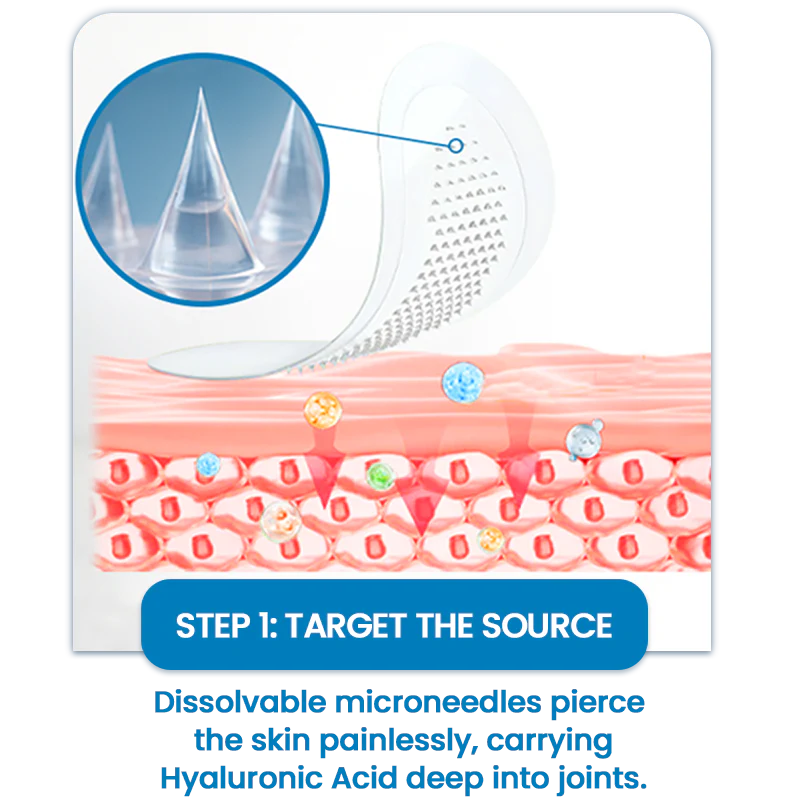

Each Alisanda® Microdart is just 0.27mm long — 10 times thinner than a needle. It penetrates only the skin’s outer barrier (stratum corneum), without reaching pain receptors or blood vessels.

➡ No pain, no bleeding — just deep, targeted delivery.

As the patch dissolves, the active ingredients penetrate the tissue — exactly where joint discomfort starts.

How It Works-Three-Step Joint Relief